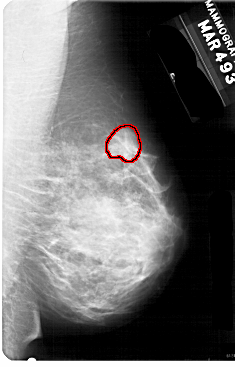

A_1752_1.RIGHT_MLO

RIGHT_MLO LINES 5491 PIXELS_PER_LINE 3511 BITS_PER_PIXEL 12 RESOLUTION 43.5 OVERLAY

FILE: A_1752_1.RIGHT_MLO.OVERLAY

TOTAL_ABNORMALITIES 1

ABNORMALITY 1

LESION_TYPE MASS SHAPE LOBULATED MARGINS OBSCURED

ASSESSMENT 4

SUBTLETY 2

PATHOLOGY BENIGN

TOTAL_OUTLINES 1

BOUNDARY